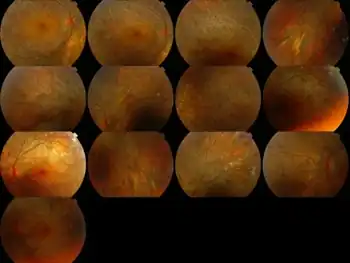

Symptoms of BCD include:

- Crystals in the cornea (the clear covering of the eye)

- Yellow, shiny deposits on the retina

- Progressive atrophy of the retina, choriocapillaries and choroid (the back layers of the eye). This tends to lead to progressive night blindness and visual field constriction.